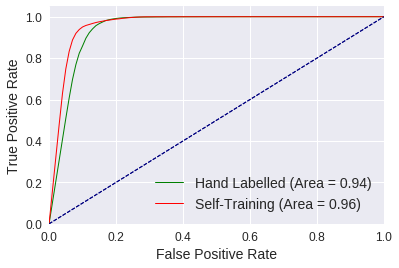

2) We empirically evaluate the ability of 3D-ConvNets [11] to detect anomalies using our initial dataset, observing average AUROC (Area Under the ROC Curve) scores of 0.94 and 0.93 for positive samples (containing anomalies) and negative (anomaly-free) samples, respectively. We also find evidence that excluding samples with motion blur improves classification accuracy.

4) Due to the small number of training samples the 3D-ConvNets over-fit after 100 epochs. To address this issue we use self-training (bootstrapping) for augmenting our dataset [30], incorporating the FC-GANs-based saliency maps into a multi-classifier voting system to automatically label additional training samples. Upon optimizing 3D-ConvNets using the additional samples we observe improved AUROC scores of 0.96 for positive and negative evaluation samples.

The ConvNets optimized with the self-training dataset significantly outperform those using only hand-labelled samples, as evident from the time-series plots depicted in the first row of Table 3. Furthermore, the frame range plots illustrating the mean cross entropy loss in the second row show a decrease in error across all evaluation sets. This translates to an increase in prediction accuracy for challenging rejects, achieving 85.1% between frame range 40 to 100. Furthermore, the overall accuracy for evaluation sets of 88.7% between frames 80 and 100 increases to 90.5%. Finally, we compute the AUROC for both approaches using samples between frame ranges 40 and 120. Self-training achieves an AUROC of 0.96 for positive and negative samples, compared to 0.94 and 0.93 when only using the hand-labelled dataset (see Figure 5). This evidence supports that disagreeing classifiers can be used under strict and lenient classification conditions, to automatically label and add samples to a dataset while providing sufficient sample variance for learning improved models.

2) Using this dataset we train ten randomly initialized 3D-ConvNets, where upon computing the AUROC we observe scores of 0.94 and 0.93 for positive (anomaly containing) and negative (anomaly-free) samples, respectively.

4) Given the small size of our dataset, we use self-training, automatically labelled 20-frame samples. To reduce the likelihood of noisy labels we use a voting system that also makes use of the FC-GANs based saliency maps to determine when classifiers are in agreement regarding an anomaly’s location. Classifiers trained with the augmented dataset achieve AUROC scores of 0.96 for both positive and negative samples, improving on the benchmarks set by 3D-ConvNets using our unaugmented dataset (See Table 3 and Figure 5).